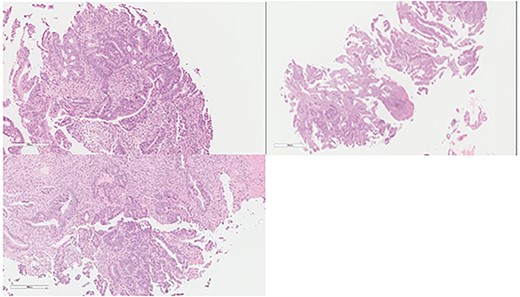

An otherwise healthy 73-year-old male, presented with rectal bleeding 6 months back. Colonoscopy revealed a sigmoid colon mass about 25 cm from the anal verge extending 10 cm proximally and a biopsy confirmed invasive adenocarcinoma (Fig. 1) Computed tomography of the abdomen and pelvis revealed a circumferential wall thickening involving the distal colon/proximal sigmoid colon spanning for 6 cm with maximum thickness of 2.3 cm, and it was also associated with surrounding fat stranding and multiple regional lymph nodes. Liver lesions were described as ill-defined hypodense lesions in two segments. The first lesion was seen in segment 7 measuring 6 × 7.5 cm and the other was seen in segment 5 measuring 6 × 3 cm (Fig. 2). Furthermore, chest CT showed no lung metastasis and a carcinoembryonic antigen level of 24.8. Eventually, a diagnosis of metastatic sigmoid adenocarcinoma with liver lesions was made. The multidisciplinary team decided to start the patient on Nac and then the case was reassessed for further resection. After completing five cycles FOLFOX, a CT of chest, abdomen and pelvis was performed for evaluating the response. The primary descending colon tumor demonstrated reduction in bulk with persistent serosal irregularity and no definitive regional lymphadenopathy was detected. The hepatic lesions revealed a partial response; in segment 7, the lesion is currently measuring 3.9 cm and in segment 5, the lesion measures 2.7 cm. Partial response to therapy was noted by a 41% reduction in sum tumor burden as per RECIST criteria (Fig. 3). The clinical tumor node metastasis classification post chemo was calculated to be T2N0M1 for descending colon cancer along with a CEA of <1.7. Despite not adding a biological agent with the systemic therapy which is the standard protocol in metastatic CRC, the patient achieved a remarkable reduction in tumor burden. The patient underwent a laparotomy with a low anterior resection of the rectum and anastomosis, synchronous resection of segments 6 and 8 of the liver along with a right-sided diaphragmatic stripping.

Colon: status of pre NAC: colonic mucosa with an infiltrative malignancy formed by tubules and gland of epithelial cells with high nucleus to cytoplasm ratio. The cells are large with frequent mitosis.